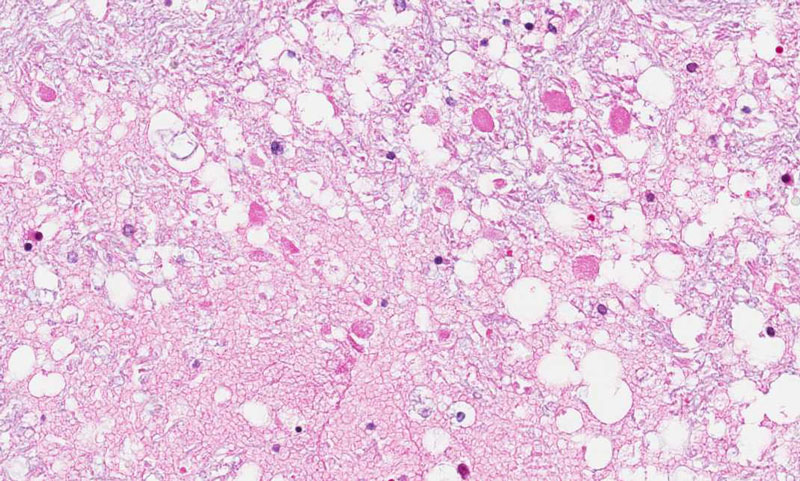

Hematoxylin & eosin

Area 3: In this area, the brain is necrotic but is not involved by the microorganism or inflammation. The reason for the necrosis is compromised circulation probably secondary to the systemic problem and the meningitis.